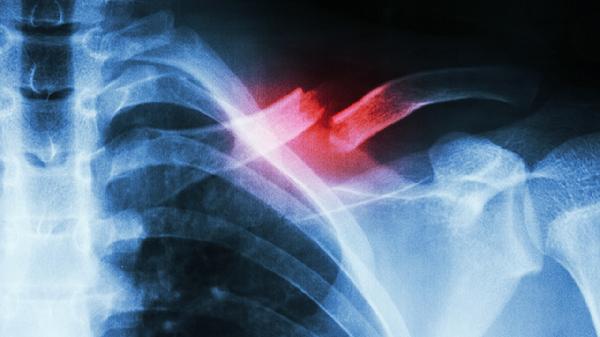

肋骨骨折引起的气胸可以自愈吗

肋骨骨折引起的气胸通常需要医疗干预,无法完全自愈。气胸是由于肋骨骨折导致胸膜破裂,空气进入胸腔,压迫肺部,影响呼吸功能。治疗包括胸腔引流、吸氧、止痛药物以及必要时的手术修复。